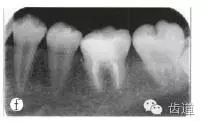

口腔檢查:6近中牙合面洞,暫封完整,叩痛(+),捫診(-),牙周組織未見明顯異常,無竇道。輔助檢查:X線根尖片示6隨遠(yuǎn)中根尖周低密度影,牙周膜增寬,遠(yuǎn)中根管內(nèi)根管外連續(xù)高密度影像(疑似器械分離影像)(圖1a)。診斷:6慢性根尖周炎。

圖1a術(shù)前x線根尖片;